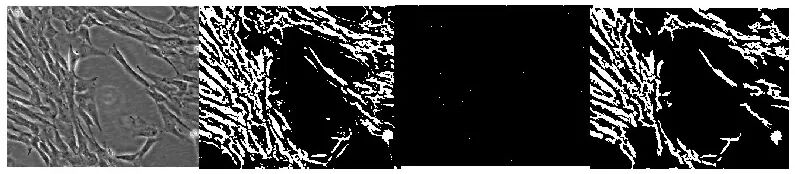

利用平台开发工具和算法,开展了一系列实验研究,我们通过卷积神经网络和反向传播神经网络技术,建立了细胞形态学参数的获取方法。

这些图片,从左到右,最左边的为原始图片,第2张图片为预处理结果,第3张为内部高密度物质提取结果,第4张为完整的细胞重建结果。

研究表明,我们的工具和方法具有可行性,能够通过图像获取 细胞形态学参数。我们团队还继续做了细胞功能与物理形态关联的研究,比如,细胞尺寸、细胞内部复杂程度与细胞质量的关系。研究发现,细胞尺寸、内部复杂程度与细胞质量有较强的相关性。

主要研究成果已经公开发表。利用数字孪生技术结合轻量深度学习(卷积神经网络CNN)技术,实现对干细胞图像分割识别、追踪[1];应用反向传播神经网络(BPNN)边缘计算,选取细胞形态学参数“周长、面积、圆度、平均直径、长、宽” 去识别目标细胞,并对研究细胞进行计数,预测结果与实际数据非常接近,证明方法可行[2]。